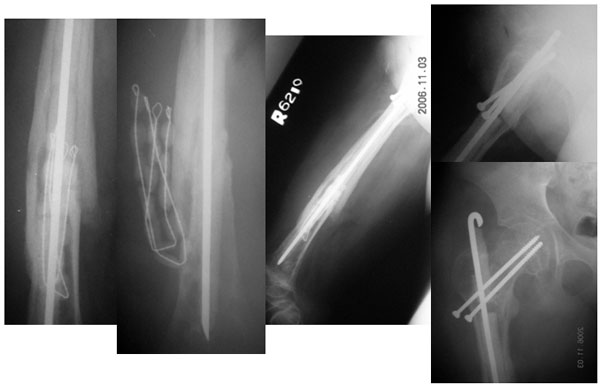

| 5 Months Post Op |

| The X-ray pictures 5 months after the surgery. These were actually taken prior to removal of the antibiotic cement beads. The fractures have healed well, the infection is also settled, with no signs of recurrence and no signs of loosening of the implants. |